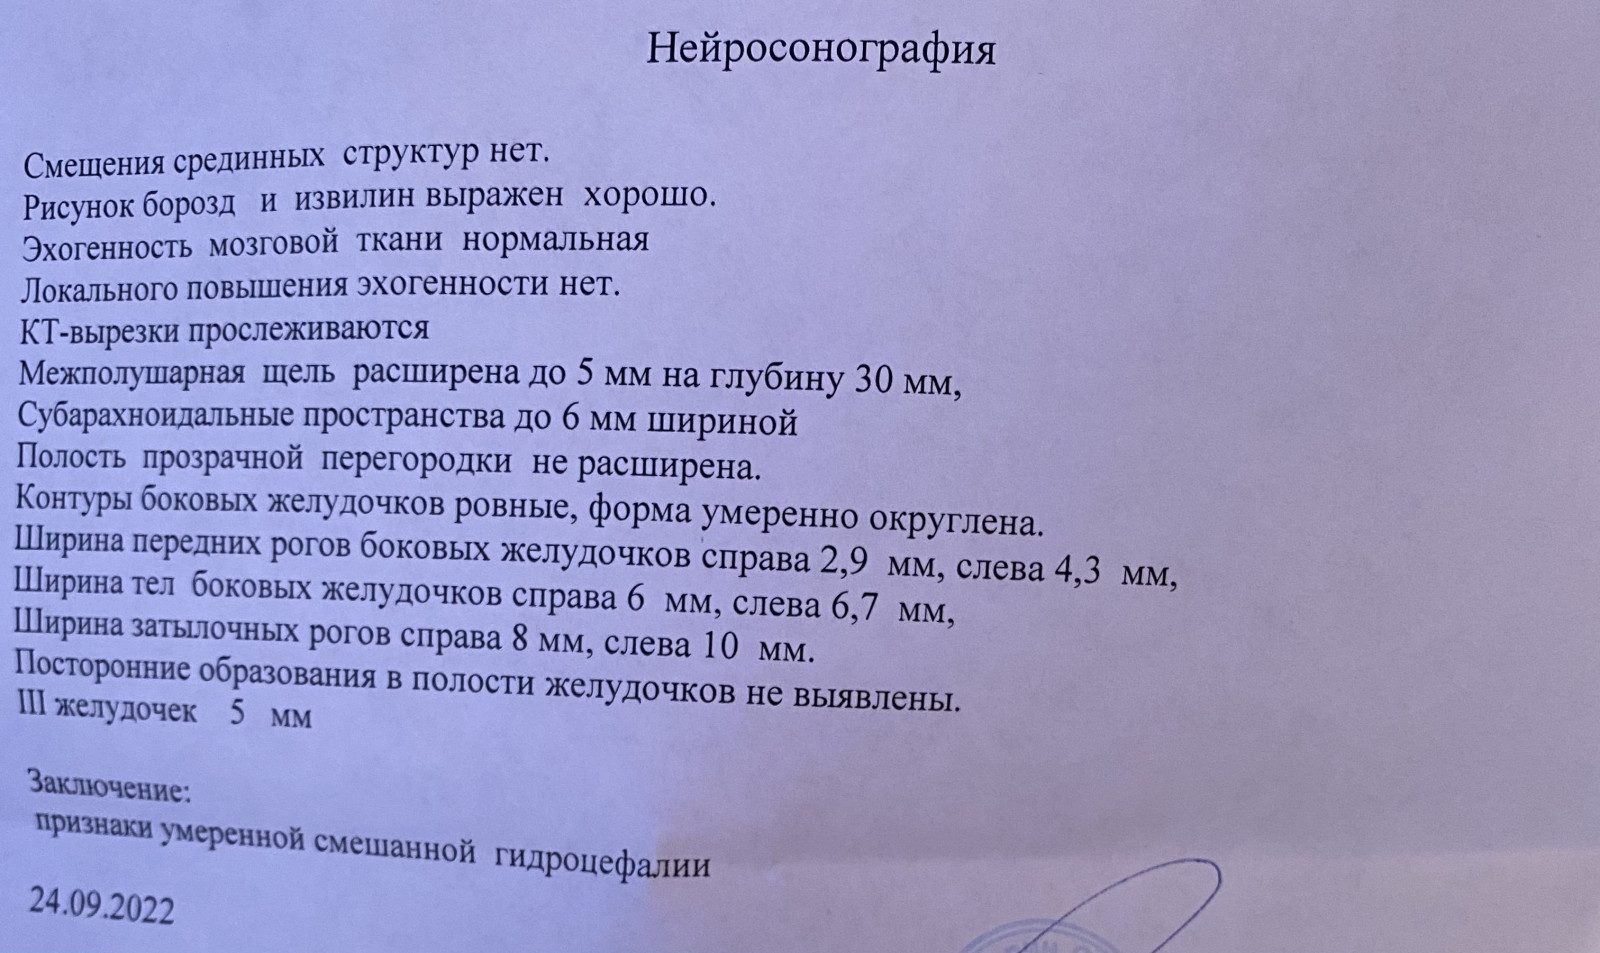

Признаки умеренно выраженной наружная

Признаки умеренно выраженной наружная 113 фото